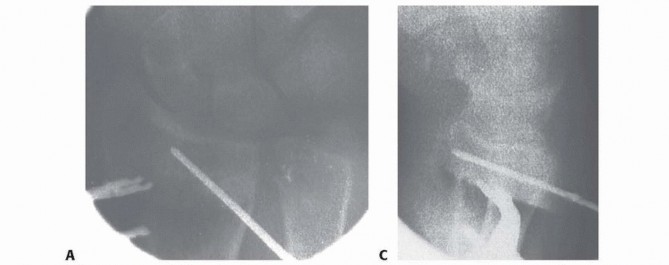

### FIG 2 • A,B. Anteroposterior (AP) and lateral radiographs of extraarticular dorsally angulated malunion. C,D. PA and lateral radiographs of an extra-articular dorsally displaced malunion. E. CT shows rotational deformity associated with a volarly displaced extra-articular fracture. (Copyright Diego Fernandez, MD, PhD.) Lack of motion should be clearly due to malalignment and not due to pain or protectiveness—likewise for instability of the DRUJ. Range of motion: A goniometer is used to measure wrist flexion, extension, radial and ulnar deviation, supination, and pronation. Ulnocarpal compression: The carpus is forcefully ulnarly deviated toward the ulna. Consistent reproduction of usual pain with ulnar deviation tasks is consistent with ulnocarpal impaction. The examiner can test for DRUJ instability by stabilizing the radius and trying to subluxate the distal ulna dorsal and volar from the sigmoid notch of the radius. Substantially, less stability than the opposite side may correlate with symptomatic DRUJ instability, but this is a very difficult and subjective test. Scaphoid shift test: Instability compared to the opposite wrist would indicate a possible scapholunate interosseous ligament tear, indicating a potential dissociative rather than the typical nondissociative carpal malalignment usually associated with distal radius malunion. Grip strength is one of the measure of wrist dysfunction, but it is largely determined by pain and effort—both strongly influenced by psychosocial factors. ## IMAGING AND OTHER DIAGNOSTIC STUDIES PA and lateral radiographs of the wrist ( FIG 2A-D) can be supplemented by specific radiographs for evaluation of the joint surface, particularly for potential articular malunions. Comparison with the opposite, uninjured wrist is useful and serves as a template for surgical correction. CT, particularly three-dimensional CT, is useful to precisely evaluate the joint surfaces ( FIG 2E). Neurophysiologic tests (nerve conduction velocity and electromyography) are ordered to evaluate any symptoms or signs of carpal tunnel syndrome that may need to be addressed. 144 ## DIFFERENTIAL DIAGNOSIS Stiffness: capsular stiffness and tendon adhesions Numbness: idiopathic carpal tunnel syndrome Pain: another discrete source of pain or even nonspecific pain ## NONOPERATIVE MANAGEMENT Nonoperative management is appropriate for low-demand and infirm individuals. Splints are weaned after 6 weeks of cast immobilization. Patients who struggle to regain motion may benefit from working with an occupational therapist or a certified hand therapist. Normal activities are resumed in 3 or 4 months. The patient may return every 2 or 4 months or so until satisfied with the result. Patience is warranted in many situations, particularly for patients with ulnar-sided wrist pain thought to be due to an extra-articular malunion. This discomfort is the last pain to go away after a distal radius fracture and can last up to a year. ## SURGICAL MANAGEMENT Surgery is appropriate when a radiographic deformity correlates with a specific anatomically correctable problem and the deformity is associated with a substantial risk of dysfunction or arthrosis. The patient must understand the risks and benefits of intervening. The surgeon should be wary of pain as the primary complaint because pain is strongly influenced by psychosocial factors, and pain relief is an achievable goal only when consistent with an objective, correctable anatomic deformity such as discomfort clearly associated with a substantial ulnocarpal impingement. When the issue is restriction of motion and there is less than 20 degrees of dorsal tilt or less than 5 mm of ulnar positive variance, a nonoperative approach may be warranted.